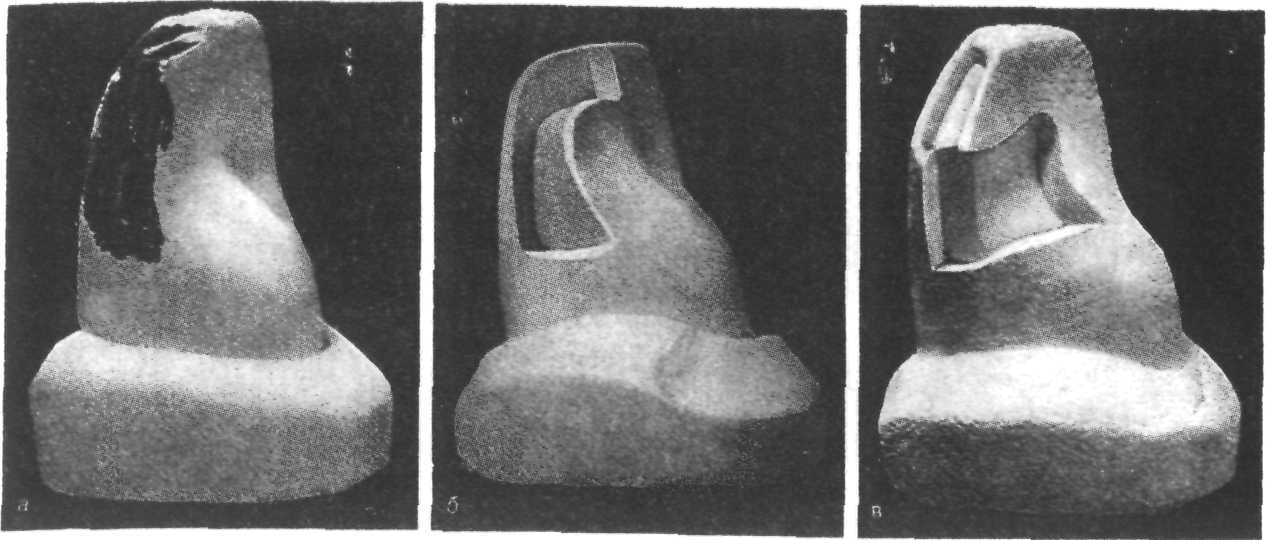

Препарирование кариозных полостей III класса: пошаговое руководство с фото